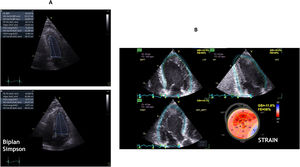

Left ventricular ejection fraction (LVEF) (Fig. 1A)Depending on the origin of CS and initial state of the cardiac function, TTE can be used for tracking LVEF evolution. Visual assessment by a simple eyeballing of LVEF is considered to be reliable in Cardiovascular Intensive Care Unit, when used by trained practitioners2 (Videos 1, 2).

Additionally, LVEF can be measured by the Simpson’s Biplane Formula,4 requiring area tracing of left ventricle (LV) cavity and contouring the endocardial border in both the apical four-chamber and two-chamber views in end-diastole and end-systole. LV is considered to have the shape of a cone. Area tracings of the LV cavity divide it into a number of discs (usually 20) and the total of volume of these discs is equal to LV volume. The difference between diastolic and systolic disc volumes divided by the diastolic volume gives LVEF value. In other words:

More precise methods have been developed during the past decades for a better quantification of global and regional myocardial function, as the Strain, Strain Rate and Speckle Tracking (Fig. 1B). These methods can track the motion and the deformation of the myocardium during systole and diastole and point out regional wall motion abnormalities (RWMA) that are not visible on visual echocardiography. LV Global Longitudinal Strain alteration precedes the LVEF one and was demonstrated to be strongly correlated to mortality.4